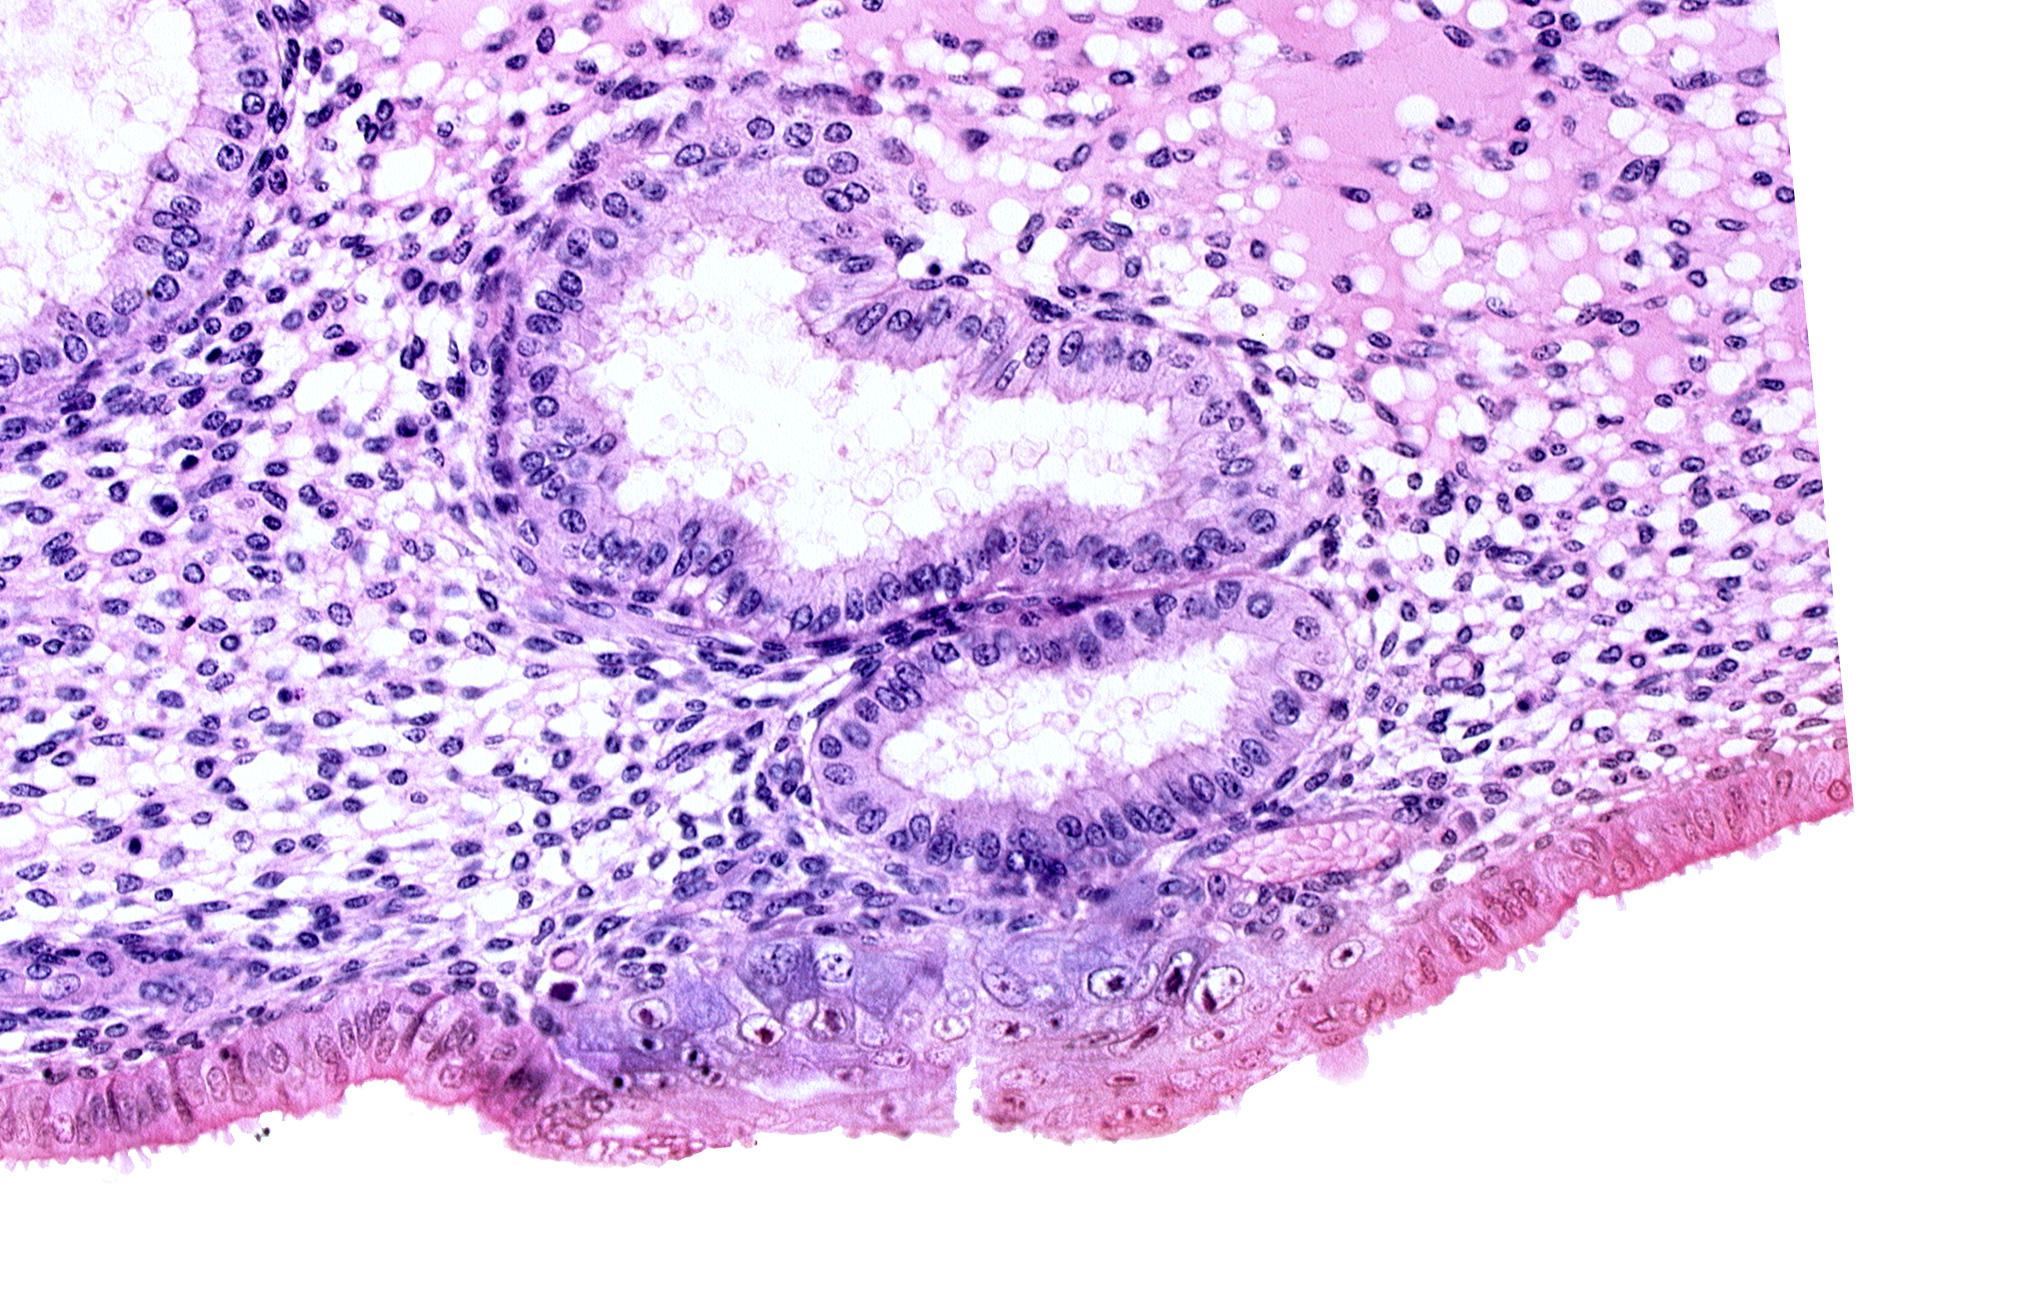

0 μm

Carnegie Embryo #8020 | Location: 06-04-07

Keywords: cytotrophoblast, edematous endometrial stroma (decidua), edge of blastocystic cavity (blastocoele), endometrial epithelium, endometrial gland, solid syncytiotrophoblast, uterine cavity

Source: The Virtual Human Embryo.